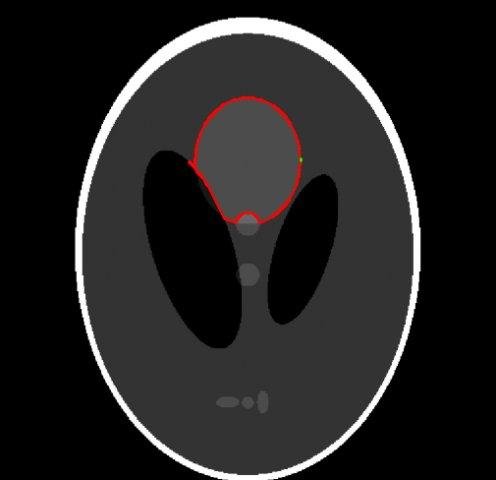

This work was a project done in course of the Summer School on Image Processing 2006 (SSIP) in Szeged,Hu. Performs a snake algorithm on 512x512. Image processing tasks are done with OpenCV and the GUI is implemented with Qt4.1.